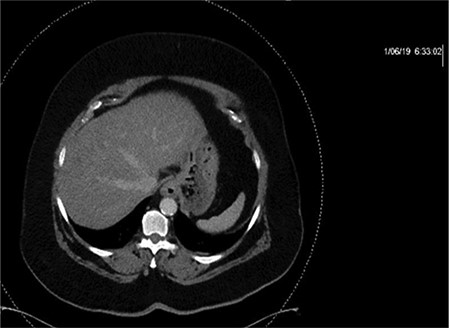

CT of the abdomen and pelvis with IV contrast was performed within 2 h of presentation. The scan showed “indeterminate, scattered ill-defined hypo-enhancing lesions in the liver with no acute etiology identified to explain the patient’s abdominal pain” (Figs 1, 3, 5). The remainder of the CT was unremarkable. Ultrasound (US) of the abdomen was negative. Because the CT and US did not identify an etiology for the patient’s abdominal pain, the working diagnosis at that time was an intestinal obstructive process.

CT with IV contrast taken at 0633 which shows ill defined, hypo-enhanced lesions of the liver.